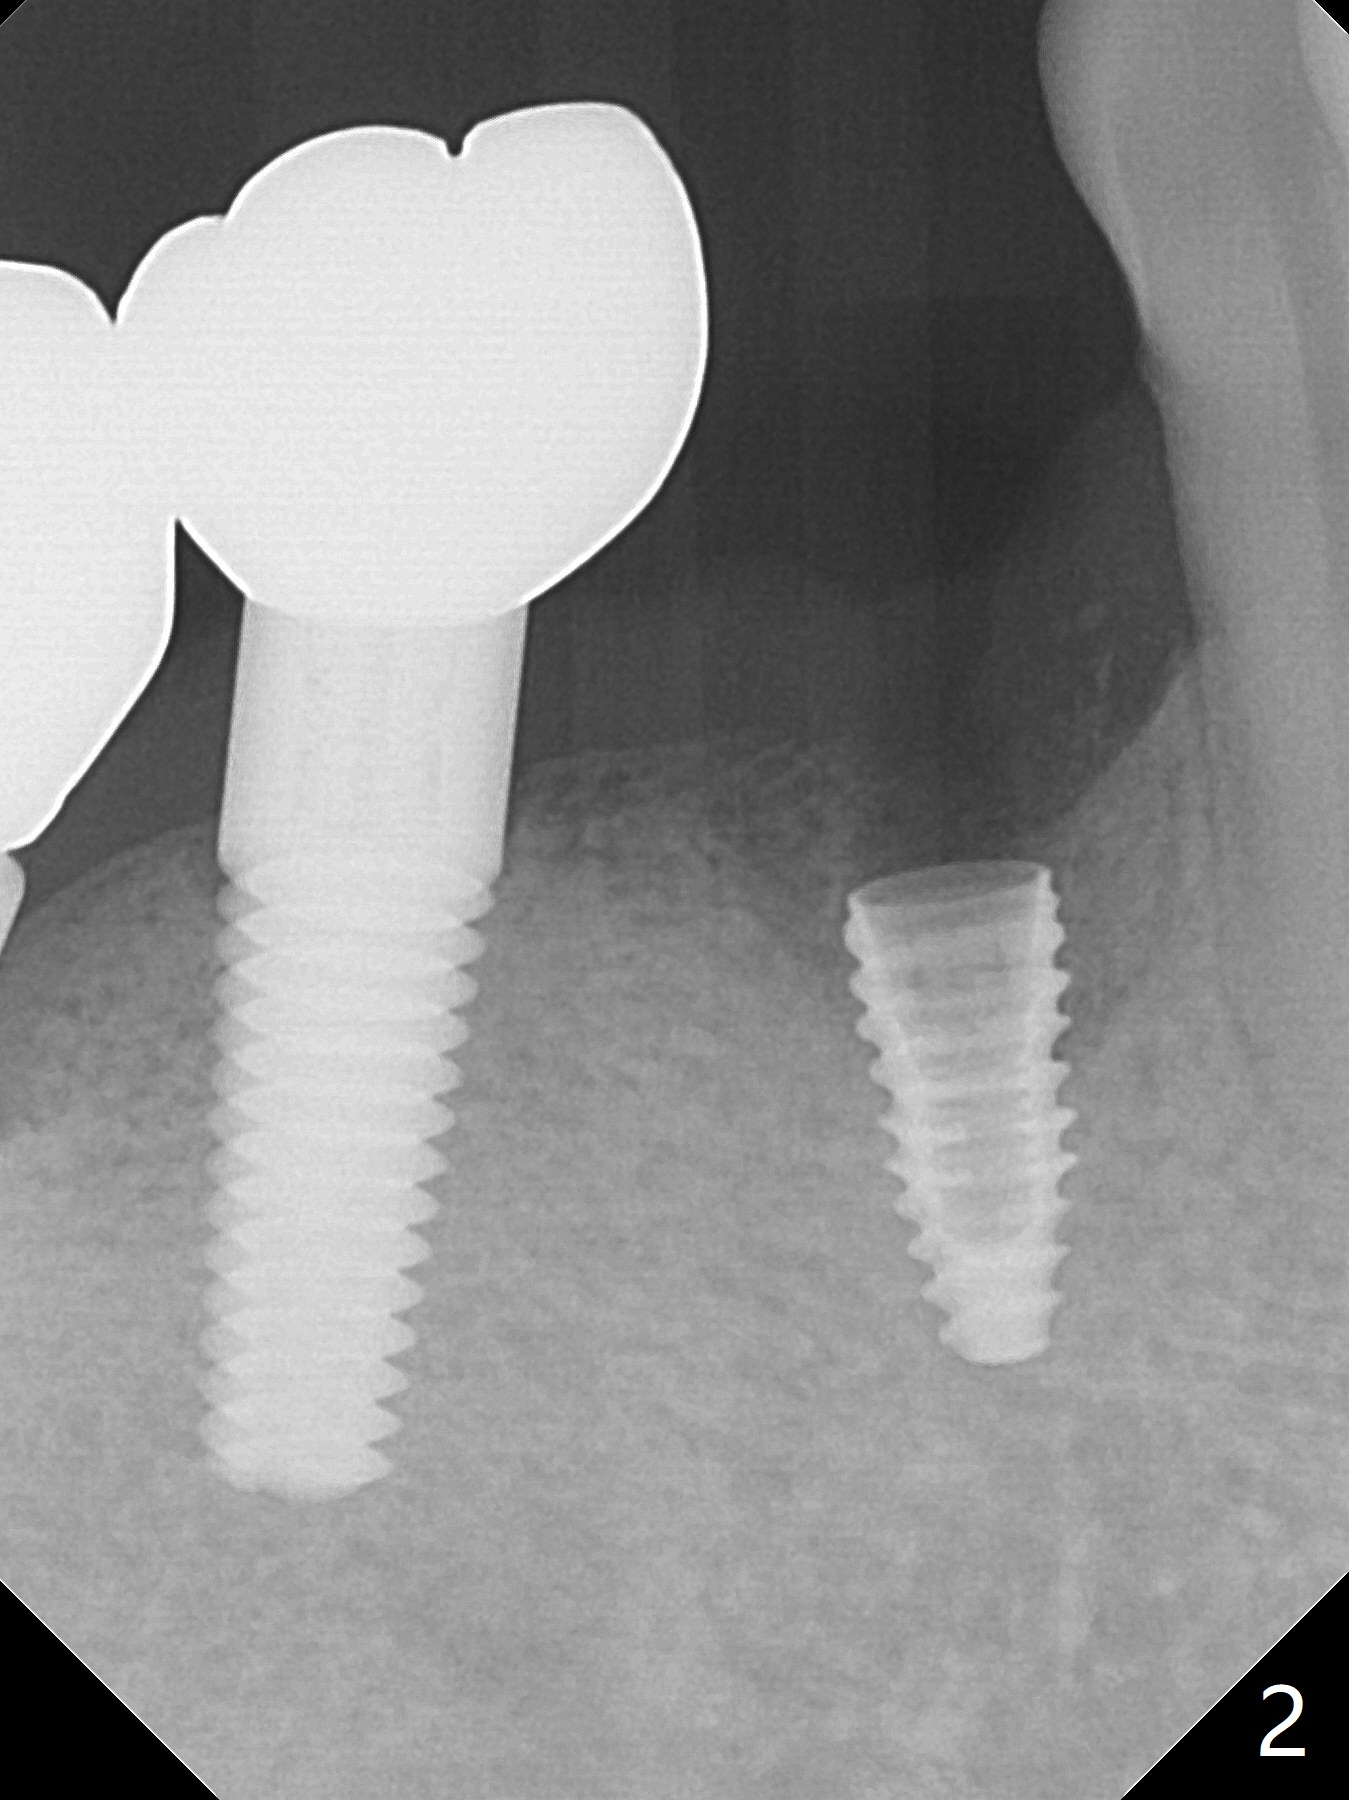

Six months post implant removal and bone graft, the patient returns for #29 implant placement with guide. With Lidocaine and Septocaine each carpule (infiltration), the patient experiences pain when the last drill used is ~ 2 mm short of designed depth. To make sure to have lingual subcrestal placement and avoid the Mental Loop, a 3.5x8.5 mm implant is placed (Fig.1,2 (3 mm shorter than the design)). Immediately postop CBCT (sagittal section) shows that the osteotomy probably hits the branch from the Mental Nerve (Fig.3 <). The coronal portion of the implant is covered with apparently grafted bone (Fig.4 <; bone density ~ 1,000 Hounsfield units; L: lingual). The implant will be loaded longer than 4 months due to unfavorable crown/implant ratio.